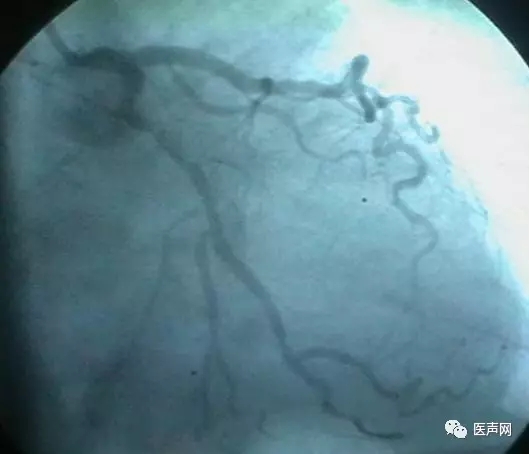

病例4:LAD PCI术后,对角支远端病变

此病变上次PCI不成功,因为LAD有支架,导丝穿过支架网眼入对角支有困难(对角支发出角度很大,成直角(箭头所示)。此次不再尝试,要学会放弃。

见下图: